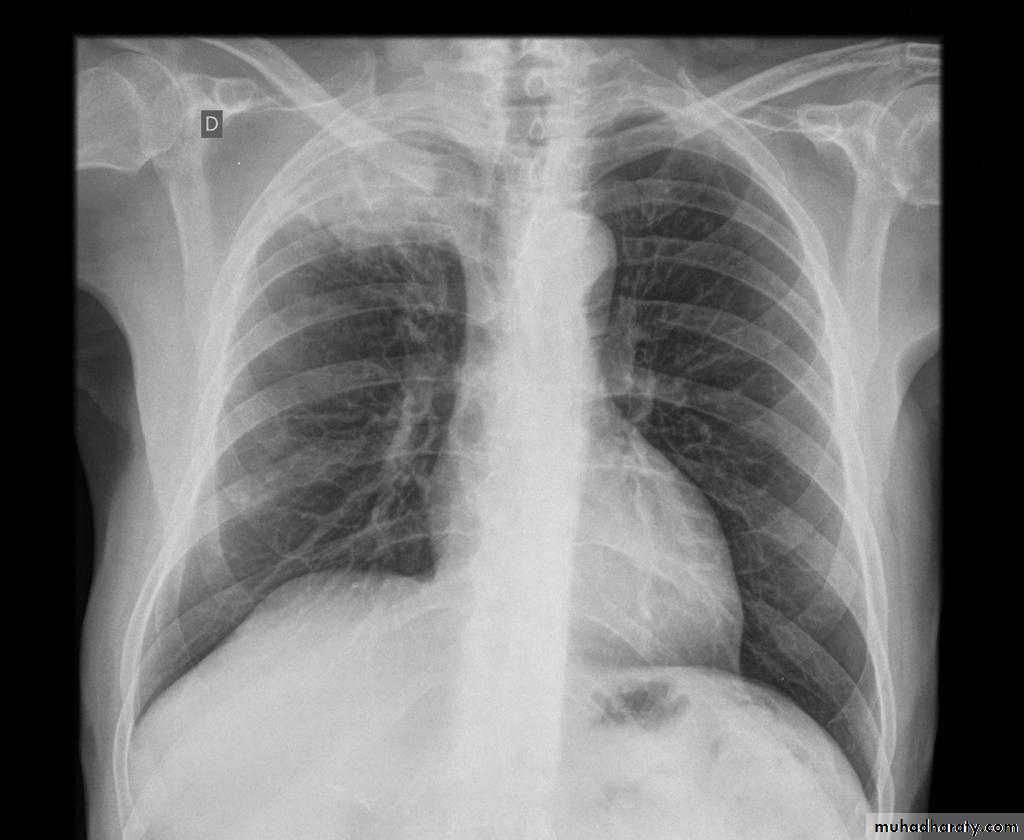

Severe dyspnea with shock